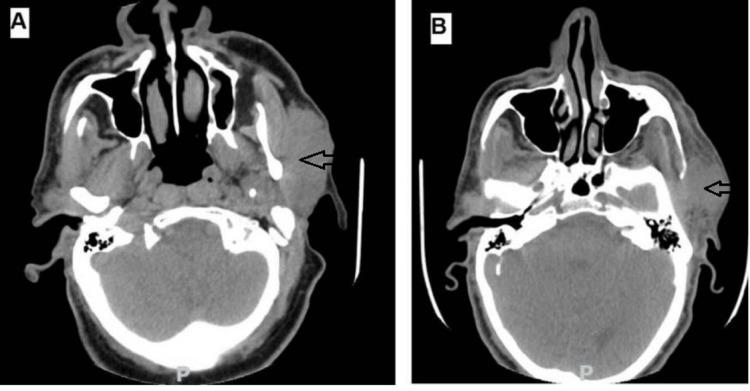

Basal cell adenoma is encountered in the salivary glands, particularly the parotid gland; however, malignant transformation is rare, and recurrence is much rarer. We report the case of a 60-year-old man who had experienced a slow-growing mass in the parotid gland, which was suspected to be pleomorphic adenoma. Radiological and cytological examination suggested an atypical lesion in the left parotid. The final diagnosis reached on the excised specimen was that of a basal cell adenocarcinoma ex adenoma with close margins. The patient presented with a recurrence after two years. Routine histopathological examination with careful examination by the pathologist is essential for proper management of such rare malignant lesions, and recurrence is a possibility. A complete excision of the tumor with tumor-free margins from the beginning is suggested.

基底细胞腺瘤多见于唾液腺,尤其是腮腺;然而,恶变罕见,复发则更为罕见。我们报告一例60岁男性病例,其腮腺出现缓慢生长的肿块,怀疑为多形性腺瘤。影像学和细胞学检查提示左腮腺有非典型病变。切除标本的最终诊断为腺瘤恶变的基底细胞腺癌,切缘紧密。该患者两年后复发。病理学家仔细检查的常规组织病理学检查对于此类罕见恶性病变的恰当处理至关重要,且存在复发的可能性。建议从一开始就完整切除肿瘤,确保切缘无肿瘤。